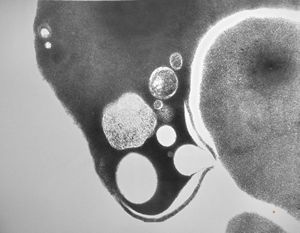

M,58y. | spleen - thesaurismosis of unknown origin … postmedicamentous?

M,44y. | spleen - Gaucher disease